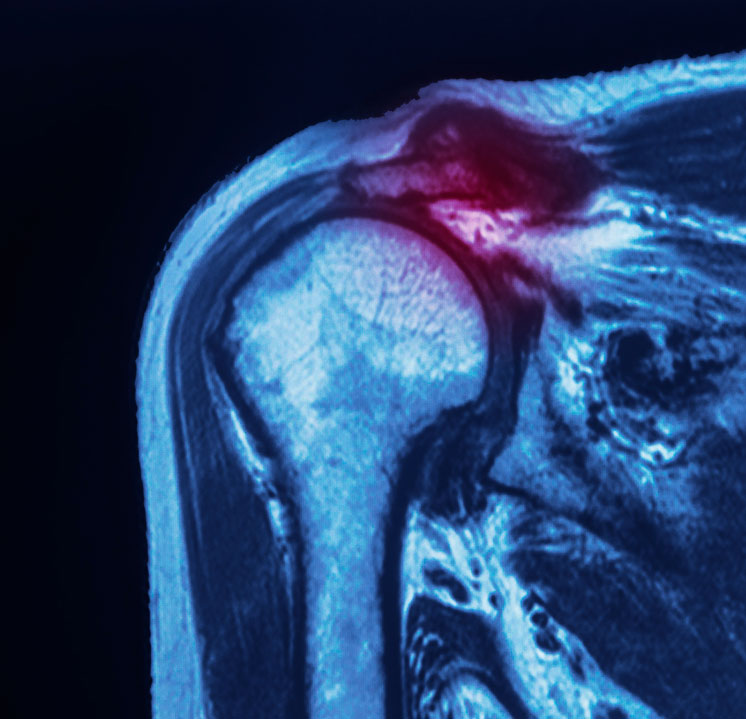

A SLAP tear is a shoulder injury that affects the superior labrum, which is a ring of cartilage around the socket of the shoulder joint. The term 'SLAP' refers to Superior Labrum Anterior and Posterior, indicating that the tear can occur in either the front (anterior) or the back (posterior) of the labrum.

The labrum is a strong, fibrous tissue that surrounds the outside edge of the glenoid and plays a crucial role in stabilising your shoulder. It deepens the socket and supports the shoulder joint by attaching many of the ligaments in the shoulder. Additionally, one of the tendons from the biceps muscle in the arm connects to the labrum.

SLAP tears can be misdiagnosed as they may resemble instability and rotator cuff disorders. Therefore, a detailed examination is necessary for an accurate diagnosis.